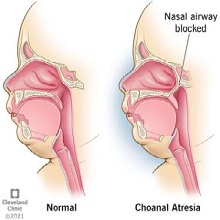

| Током викенда умерен број пацијената у ОРЛ амбуланти у Општој болници Панчево. Најчешће су долазили због компликација горњих респираторних инфекција, деца због гутања страних тела али још увек има и падова и повређивања са бицикла. |

Ринитис је запаљење носне слузокоже, које се испољава цурењем носа, кијањем или сврабом у носу. Дели се на алергијски, инфективни и друге. |

Ларингитиси су запаљења гркљана, обично се јављају у склопу запаљенских процеса дисајних путева а ређе изоловано. |